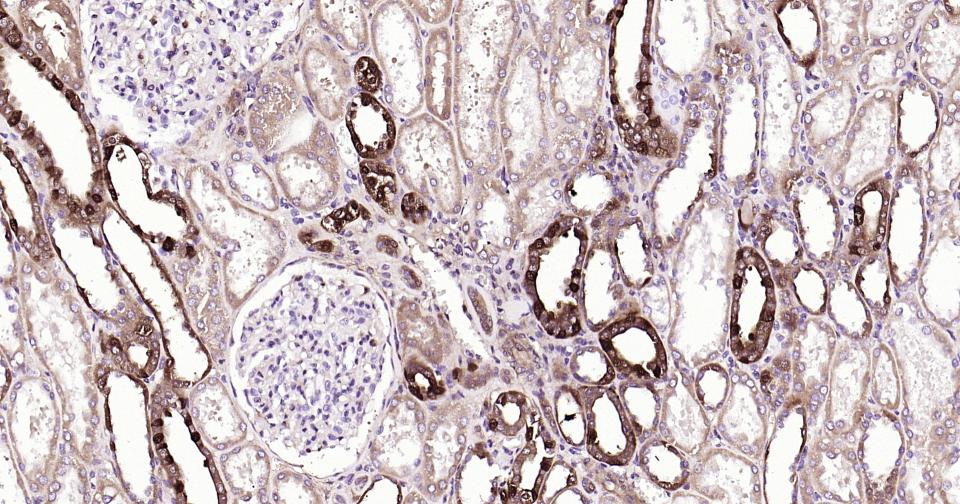

Paraformaldehyde-fixed, paraffin embedded Human Kidney; Antigen retrieval by boiling in sodium citrate buffer (pH6.0) for 15 min; Antibody incubation with Galectin 3 Monoclonal Antibody, Unconjugated(bsm-61087R) at 1:200 overnight at 4°C, followed by conjugation to the SP Kit (Rabbit, SP-0023)and DAB (C-0010) staining.